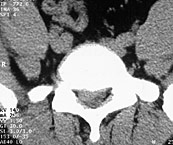

Im Vergleich zu herkömmlichen offenen Bandscheibenoperationen mit großem operativem Zugang und erhöhtem Risiko einer schmerzhaften Narbenbildung hat sich der Trend zur mikroskopisch unterstützten Bandscheibenoperationen wegen der klaren Vorteile durchgesetzt. Über einen kleinen Hautschnitt kann schonend und zugleich effektiv das hervorgetretene auf den Nerven drückende Bandscheibengewebe entfernt werden. Das bei kleinerem Hautschnitt auch eine deutlich geringere Narbenbildung auftritt liegt hierbei auf der Hand.